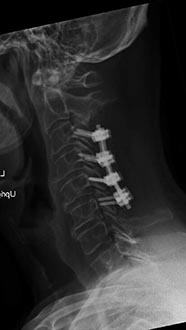

56 year old woman who presented with severe neck pain with numbness of both hands and balance problems due to severe cervical stenosis. Patient underwent C4 to C7 anterior cervical discectomy and fusion with complete resolution of her neurological symptoms.